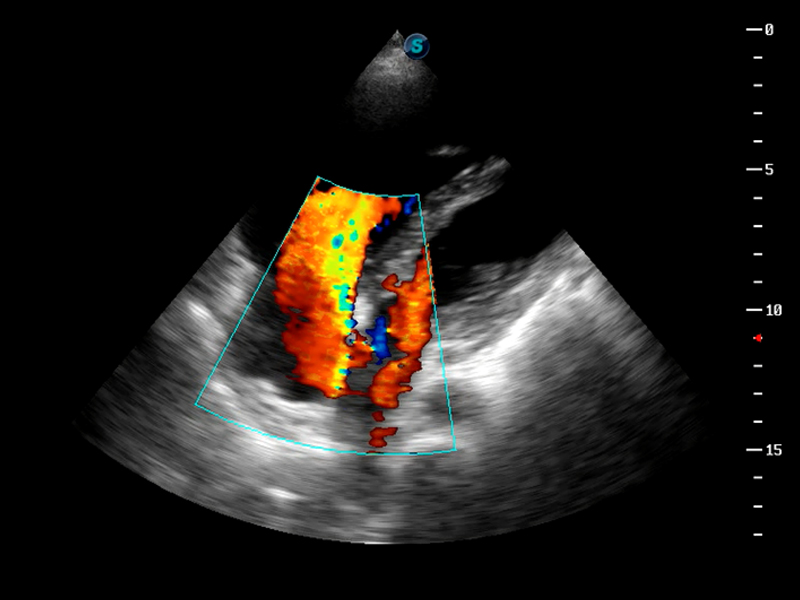

S9便携式彩色多普勒超声诊断仪是milan米兰研发的高端便携彩超设备,外观设计新颖、产品性能卓越。S9在便携超声领域采用了突破传统的触摸屏交互设计,并以先进的软件硬件技术和设计理念,为您带来清晰的图像质量、稳定的工作性能和便捷的操作体验。

AutoC智能血流追踪